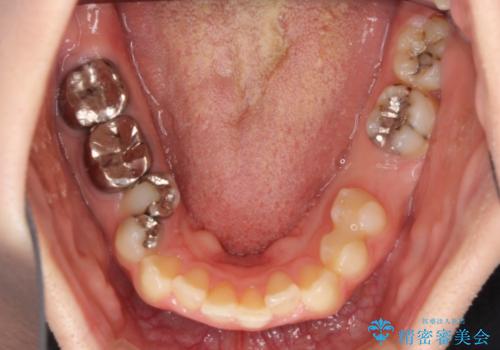

全体的にむし歯や欠損が多く、矯正治療とは別に処置が多く必要な口腔内でした。

口元の突出感を改善するために小臼歯4本を抜歯することとしましたが、左下は大臼歯が欠損していたため、そのスペースを活用し、小臼歯を3本抜歯して治療を行うこととしました。